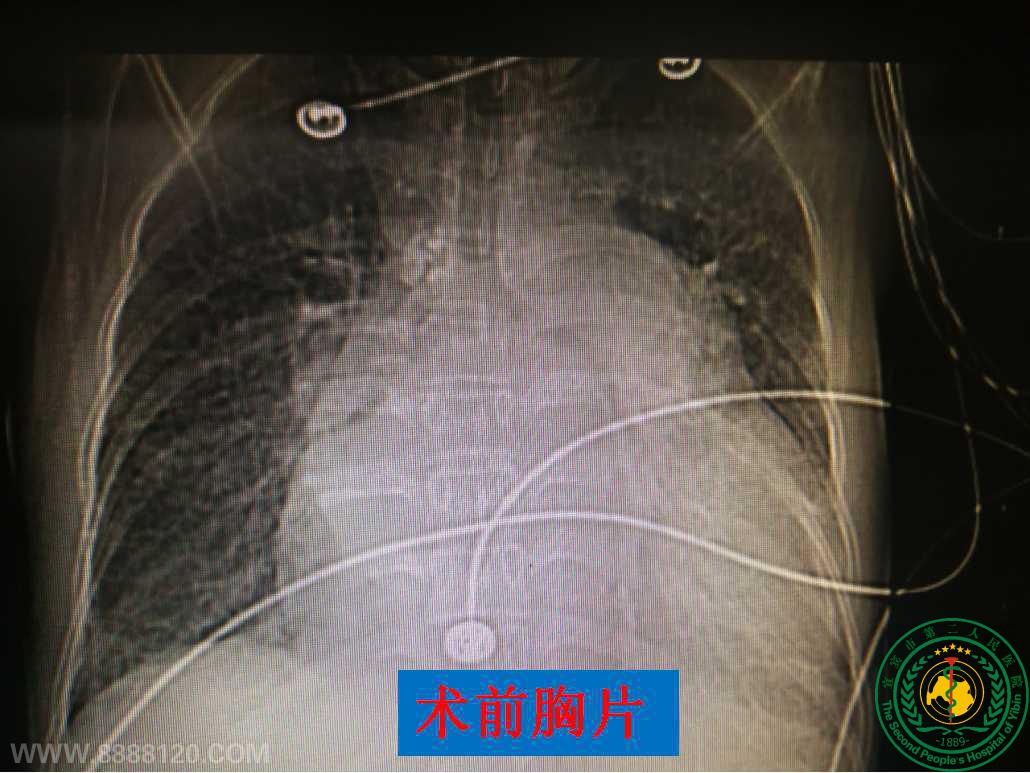

我院率先在宜宾独立完成心脏二尖瓣+三尖瓣双瓣膜置换术

我院率先在宜宾独立完成心脏二尖瓣+三尖瓣双瓣膜置换术19218